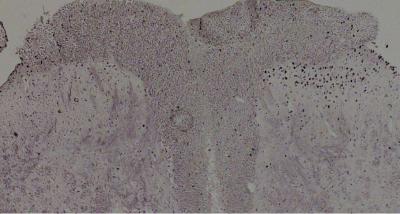

Technically, the team in which the Spanish expert works has demonstrated in mice that a population of superficial neurons in the spinal cord controls an epigenetic marker known as pS10H3.

"We observed the effect after using various animal pain models: inducing burns, applying capsaicin or electrical nerve stimulation," explains Torres Pérez. Therefore, the authors believe that, if this activation is blocked, they will achieve a new pain relief therapy.

For the Spanish researcher, "pS10H3 is a new marker of pain processing in neurons on the spinal cord, and the changes caused by it are fundamental to normal pain development, which opens up new therapeutic possibilities."